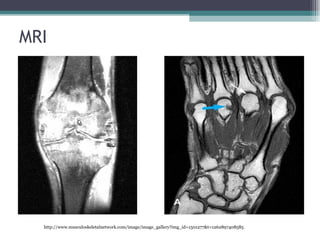

Imaging Studies  Radiography Used to see joints and extremities. Erosion in feet. MRI Is used for patients with abnormalities. Ultrasonography Allows recognition of effusion in joints and cyst. High resolution sonograms allow you to see tendons, vascularization of synovial membrane. Bone scanning Help distinguish inflamatory from non inflamatory changes. Densitometry

MRI http://www.musculoskeletalnetwork.com/image/image_gallery?img_id=1501277&t=1262897408585